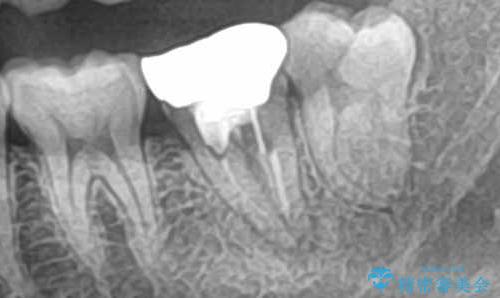

- 「歯茎の腫れ」を主訴に来院された患者様です。検査の結果、エンドペリオ病変と診断いたしました。

治療方針としては、保存的治療と抜歯後のインプラント治療の2つの選択肢をご提案させていただきました。

患者様ご自身が抜歯後のインプラント治療をご希望されたため、インプラントによる治療を行いました。

当院では、痛みの少ないインプラント治療を行っております。

実際に治療を受けられた多くの患者様からは、「腫れもなく、痛み止めをまったく使用しなかった、もしくは1〜3錠程度で済んだ」といったお声を頂いております。